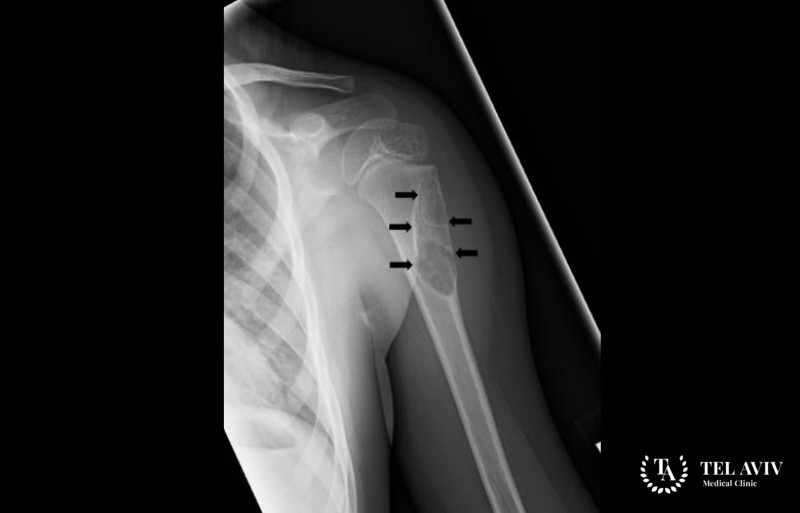

Костная киста – представляет собой патологическую полость, которая возникает в результате нарушения местного кровообращения и активации ферментов, которые вызывают разрушение костного вещества. Патология развивается медленно. Человек может не подозревать о наличии заболевания, так как симптоматика выражена слабо. По мере роста опухоли, она начинает сдавливать соседние структуры и возникает чувство дискомфорта. Данная патология является генетической мутацией или может образоваться из-за ранее полученной травмы. Зачастую врач может обнаружить заболевания у людей до 30 лет.

- Рентгенография;